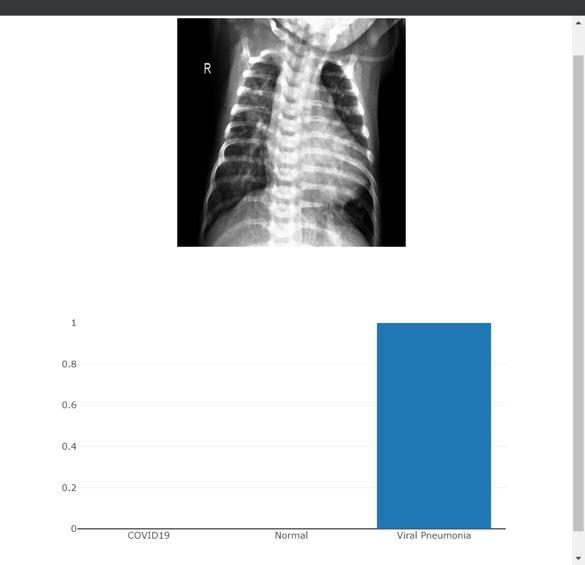

International Research Journal of Engineering and Technology (IRJET) e ISSN: 2395 0056 Volume: 09 Issue: 04 | Jun 2022 www.irjet.net p ISSN: 2395 0072 © 2022, IRJET | Impact Factor value: 7.529 | ISO 9001:2008 Certified Journal | Page 3247 Fig 3 : Selectedimage&it’spredictionforNonCovidX ray Fig 4 : SelectedImage&PredictionforCovidinfectedX ray Fig 5 : SelectedImageandpredictionforViral Pneumonia